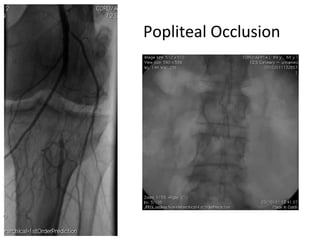

Popliteal Occlusion

Duplex: Left popliteal occlusion (Fibro-lipid plaque). Collateral flow in the BTK arteries

PTA of the Popliteal artery

1) Predilation with an undersized balloon

2) Prolonged dilation with a Drug Coated Balloon